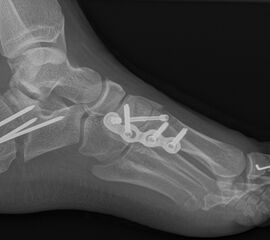

Knick-Senk-Platt-Fuß Korrektur mit dem Canalis Tarsi Spacer

In der Korrektur des schmerzhaften, aber flexiblen Knick-Senk-Fußes oder Plattfußes ist die Schraubenarthrorise mit einem Sinus tarsi oder besser bezeichnet als Canalis tarsi Spacer und alternativ mit einer Calcaneus-Stopp-Schraube seit vielen Jahren ein etabliertes Verfahren und führt zu einer kompletten Korrektur von flexiblen Knick- und Plattfuß-Fehlstellungen (Abb. 7). Die nötige Schnittlänge über dem Sinus tarsi beträgt für beide Verfahren 1 cm.

Abb. 7 a-e: Knick-Senk-Fuß prä- und postoperative Situation (a-b), ventrale und dorsale Ansicht (c-d). Laterale Ansicht des Hautschnittes über dem Sinus tarsi (e).